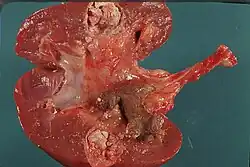

Nephrocalcinosis

Nephrocalcinosis, once known as Albright's calcinosis after Fuller Albright, is a term originally used to describe the deposition of poorly soluble calcium salts in the renal parenchyma due to hyperparathyroidism. The term nephrocalcinosis is used to describe the deposition of both calcium oxalate and calcium phosphate.[1] It may cause acute kidney injury. It is now more commonly used to describe diffuse, fine, renal parenchymal calcification in radiology.[2] It is caused by multiple different conditions and is determined by progressive kidney dysfunction. These outlines eventually come together to form a dense mass.[3] During its early stages, nephrocalcinosis is visible on x-ray, and appears as a fine granular mottling over the renal outlines. It is most commonly seen as an incidental finding with medullary sponge kidney on an abdominal x-ray. It may be severe enough to cause (as well as be caused by) renal tubular acidosis or even end stage kidney disease, due to disruption of the kidney tissue by the deposited calcium salts.